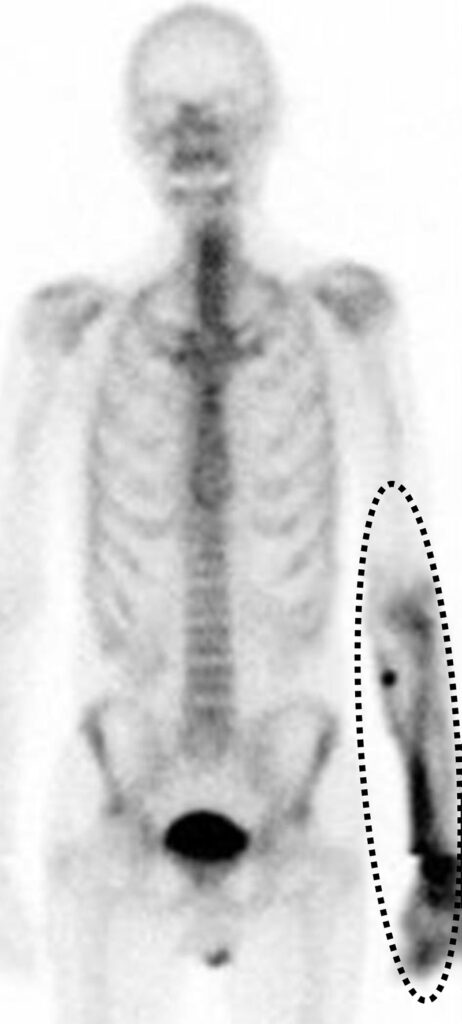

Metastasi da osteosarcoma in un uomo di 22 anni, a cui è stato recentemente diagnosticato un osteosarcoma del femore prossimale destro.

Oltre alla massiva e attesa ipercaptazione nella sede del tumore primitivo, lo studio whole-body rivela una captazione extra-ossea focale e intensa a livello dell’emitorace sinistro.

L’imaging morfologico conferma la presenza di un nodulo polmonare nel lobo superiore sinistro, caratterizzato da calcificazioni periferiche.

Le metastasi derivanti da tumori formanti osso, come l’osteosarcoma, mantengono la capacità osteogenica della lesione primaria. Esse producono matrice osteoide che calcifica, captando avidamente i radiotraccianti osteotropi (come il 99mTc-MDP) e rendendo le metastasi polmonari o dei tessuti molli ben visibili alla scintigrafia ossea.